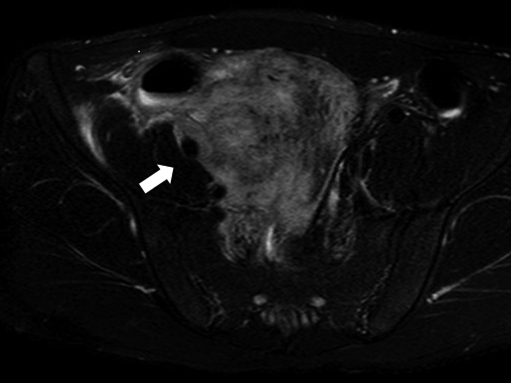

骨盤部造影MRI所見:腫瘍は85×75×100 mm大,内部は不均一でT1強調像では低~等信号,T2強調像では低~高信号が混在していた.腫瘍の境界は明瞭で,右腸腰筋とは広範囲で接しつつも境界は保たれていた.また,外腸骨動静脈とは広範囲に密接し,血管壁に沿うように存在した.回盲部を含め周囲の腸間膜脂肪織は脂肪抑制T2強調像で不均一な高信号であり,右側精索も同様の所見であった(Fig. 3).

The right external iliac artery was involved in the tumor by contrast enhanced MRI (arrow).